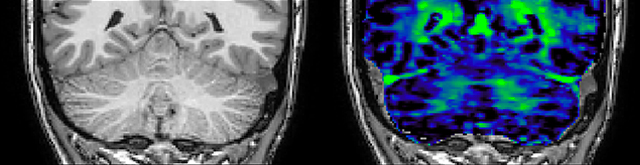

T1 - Weighted, Myelin Water Fraction Superimposed

Spinal cord coverage

Smaller, more isotropic voxels

Excellent detail in quantitative maps

Images courtesy of Adam Dvorak, Department of Physics and Astronomy, University of British Columbia

He says the accelerated scanning is achieved via the use of Compressed SENSE and MultiBand SENSE. “We can use Compressed SENSE acceleration factors of about 10 on a 3D FLAIR for instance, which is quite remarkable compared with what we saw with the Achieva. With 3D FLAIR, we can push the spatial resolution to 0.3 cubic mm and it works. Previously, our 3D FLAIR scans lasted about 8 minutes, but now with Elition they are five minutes. The SNR is also visibly better. Our SWI and QSM scans look fantastic. Also, since a lot of neuroimaging is EPI based, using the MultiBand SENSE technique can increase temporal resolution and make it possible to run complicated DTI scans relatively quickly.”

QSM based on a Compressed SENSE multi-echo SWI.